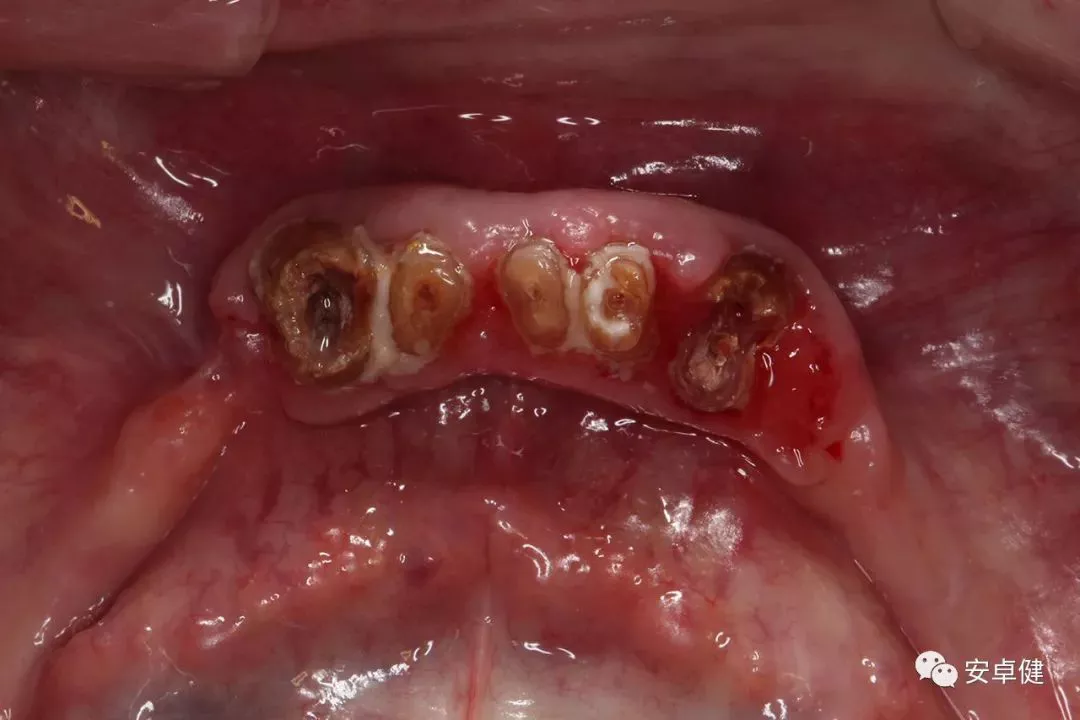

种植术前拆除下颌义齿后合面照

▷ 影像学检查

• 可见11、12、13、14、15、21、22、23、24、31、33、44、43、42、41根管内高密度影及上部烤瓷桥修复体;

• 31、33、41、42、43、44可见根尖及周围低密度暗影。

术前CBCT影像学检查

▷ 预后结果

•  上颌11、12、13、14、15、21、22、23、24烤瓷桥可继续行使功能;

•   下颌31、33、41、42、43、44无保留价值 。

•   摘除下颌活动义齿,拆除下颌前部固定义齿;

拆除下颌固定义齿后下颌合面照

•   拔除无法保留的44、43、42、41、31、33残冠;